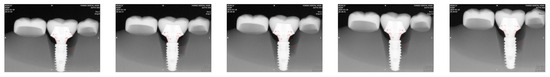

Figure 2.

The right second premolar and the second molar received lithium disilicate (LS2) ceramic restorations. LS2 was chosen due to its translucent characteristics for proximal overlap measurements.